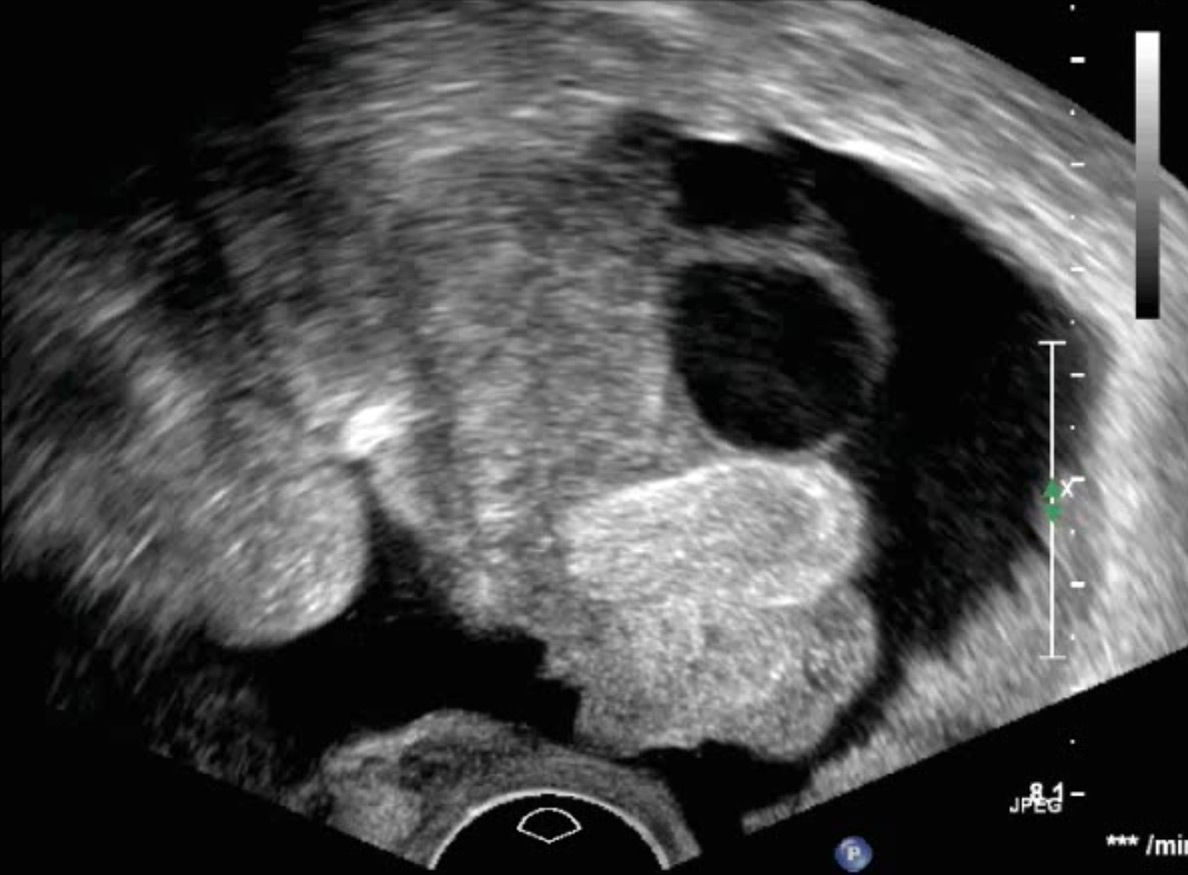

Zystischer Tumor Sonographieatlas Erlangen

Ovarien Sonographieatlas Erlangen